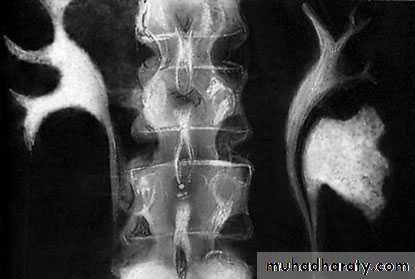

Crossed Renal Ectopia With and Without FusionHorseshoe Kidney

found in 1:1000 necropsies an is commoner in men.probably the most common of all renal fusion anomalies

The anomaly consists of two distinct renal masses lying

vertically on either side of the midline and connected at

their respective lower poles by a parenchymatous or fibrous

isthmus that crosses the midplane of the body.

Fusion of the renal masses early in embryonic life, so its ascent

will be impeded by inferior mesenteric artery.

The kidneys are low located, mal rotated and pelves lie anteriorly

Symptom When present, they are related to complications like hydronephrosis, infection, or calculus formation

Diagnosis ultrasound, IVU, CT scan

Treatment:

-Medical: pain relief and to control infection-Surgical: stone removal, PUJ stenosis correction and isthmus division in cases of

-operations on the aorta

Prognosis usually they have normal life.